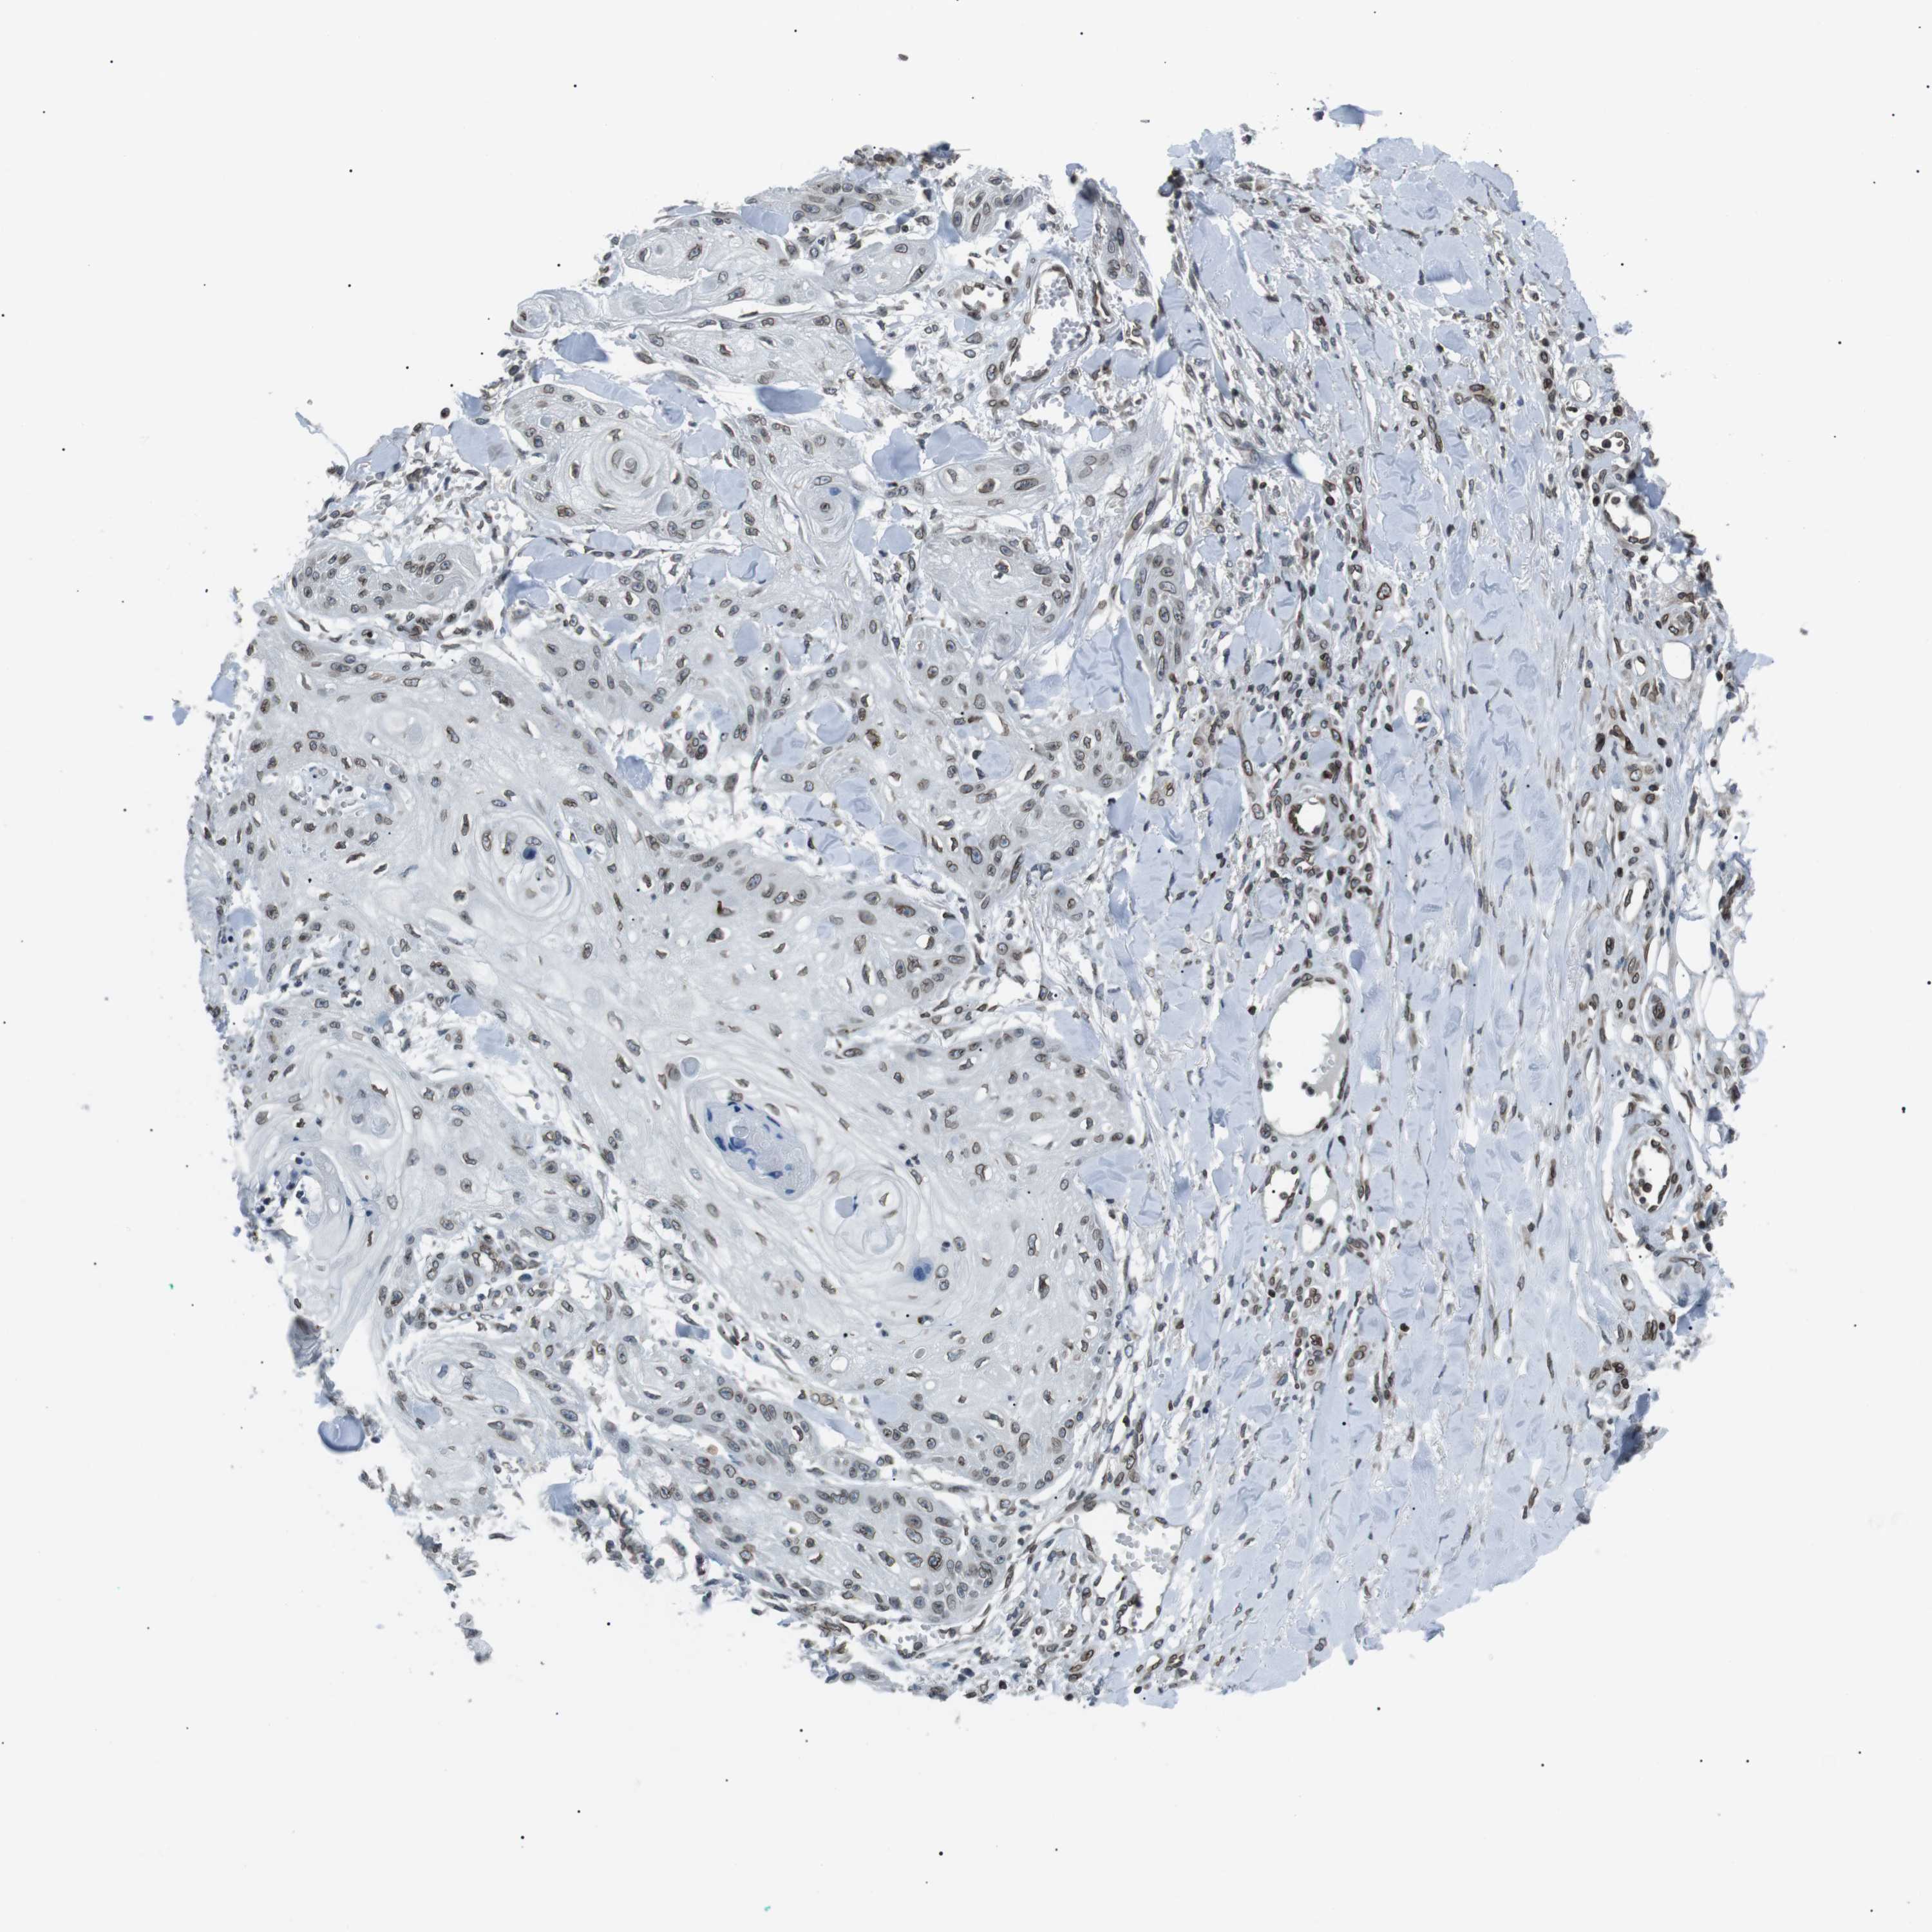

SKIN CANCER - Protein expressioni

A mouse-over function shows sample information and annotation data. Click on an image to view it in a full screen mode. Samples can be filtered based on level of antibody staining by selecting one or several of the following categories: high, medium, low and not detected. The assay and annotation is described here.

Each image is clickable and will lead to virtual microscopy that enables deeper exploration of all samples and also displays staining intensity scores, fraction scores and subcellular localization as well as patient and tissue information for each sample.

Antibody HPA015752

Staining

High

Intensity

Strong

Quantity

>75%

Location

Nuclear

Squamous cell carcinoma, NOS

Squamous cell carcinoma, metastatic, NOS